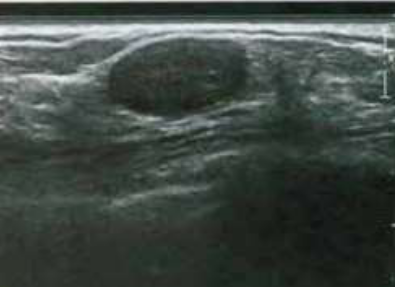

Paciente do sexo feminino, casada, nulípara, 42 anos, foi encaminhada para

avaliação ultrassonográfica das mamas, devido mamografia com classificação Birads 0. Ao exame observamos um nódulo oval, hipoecóico, sólido, paralelo à pele, contornos definidos, ausência de atenuação posterior, não se observa calcificações e o Doppler é negativo. Qual o possível diagnóstico?